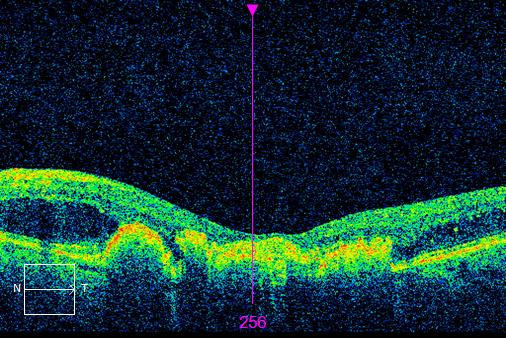

| OCT scan of the retina. The dip is a natural occurrence, where central vision is located. Imaged beneath are small, black void like spaces. These are filled with fluid and is called, macula oedema. |

It is important to rule out macula oedema as the cause of reduced vision post surgery. Patients should undergo a thorough slit lamp examination and have an OCT scan. Which immediately shows any fluid or swelling in the macula, which is the part of the retina used for central vision. Macula oedema or fluid in the retina is a possible complication of surgery and should be checked an monitored.